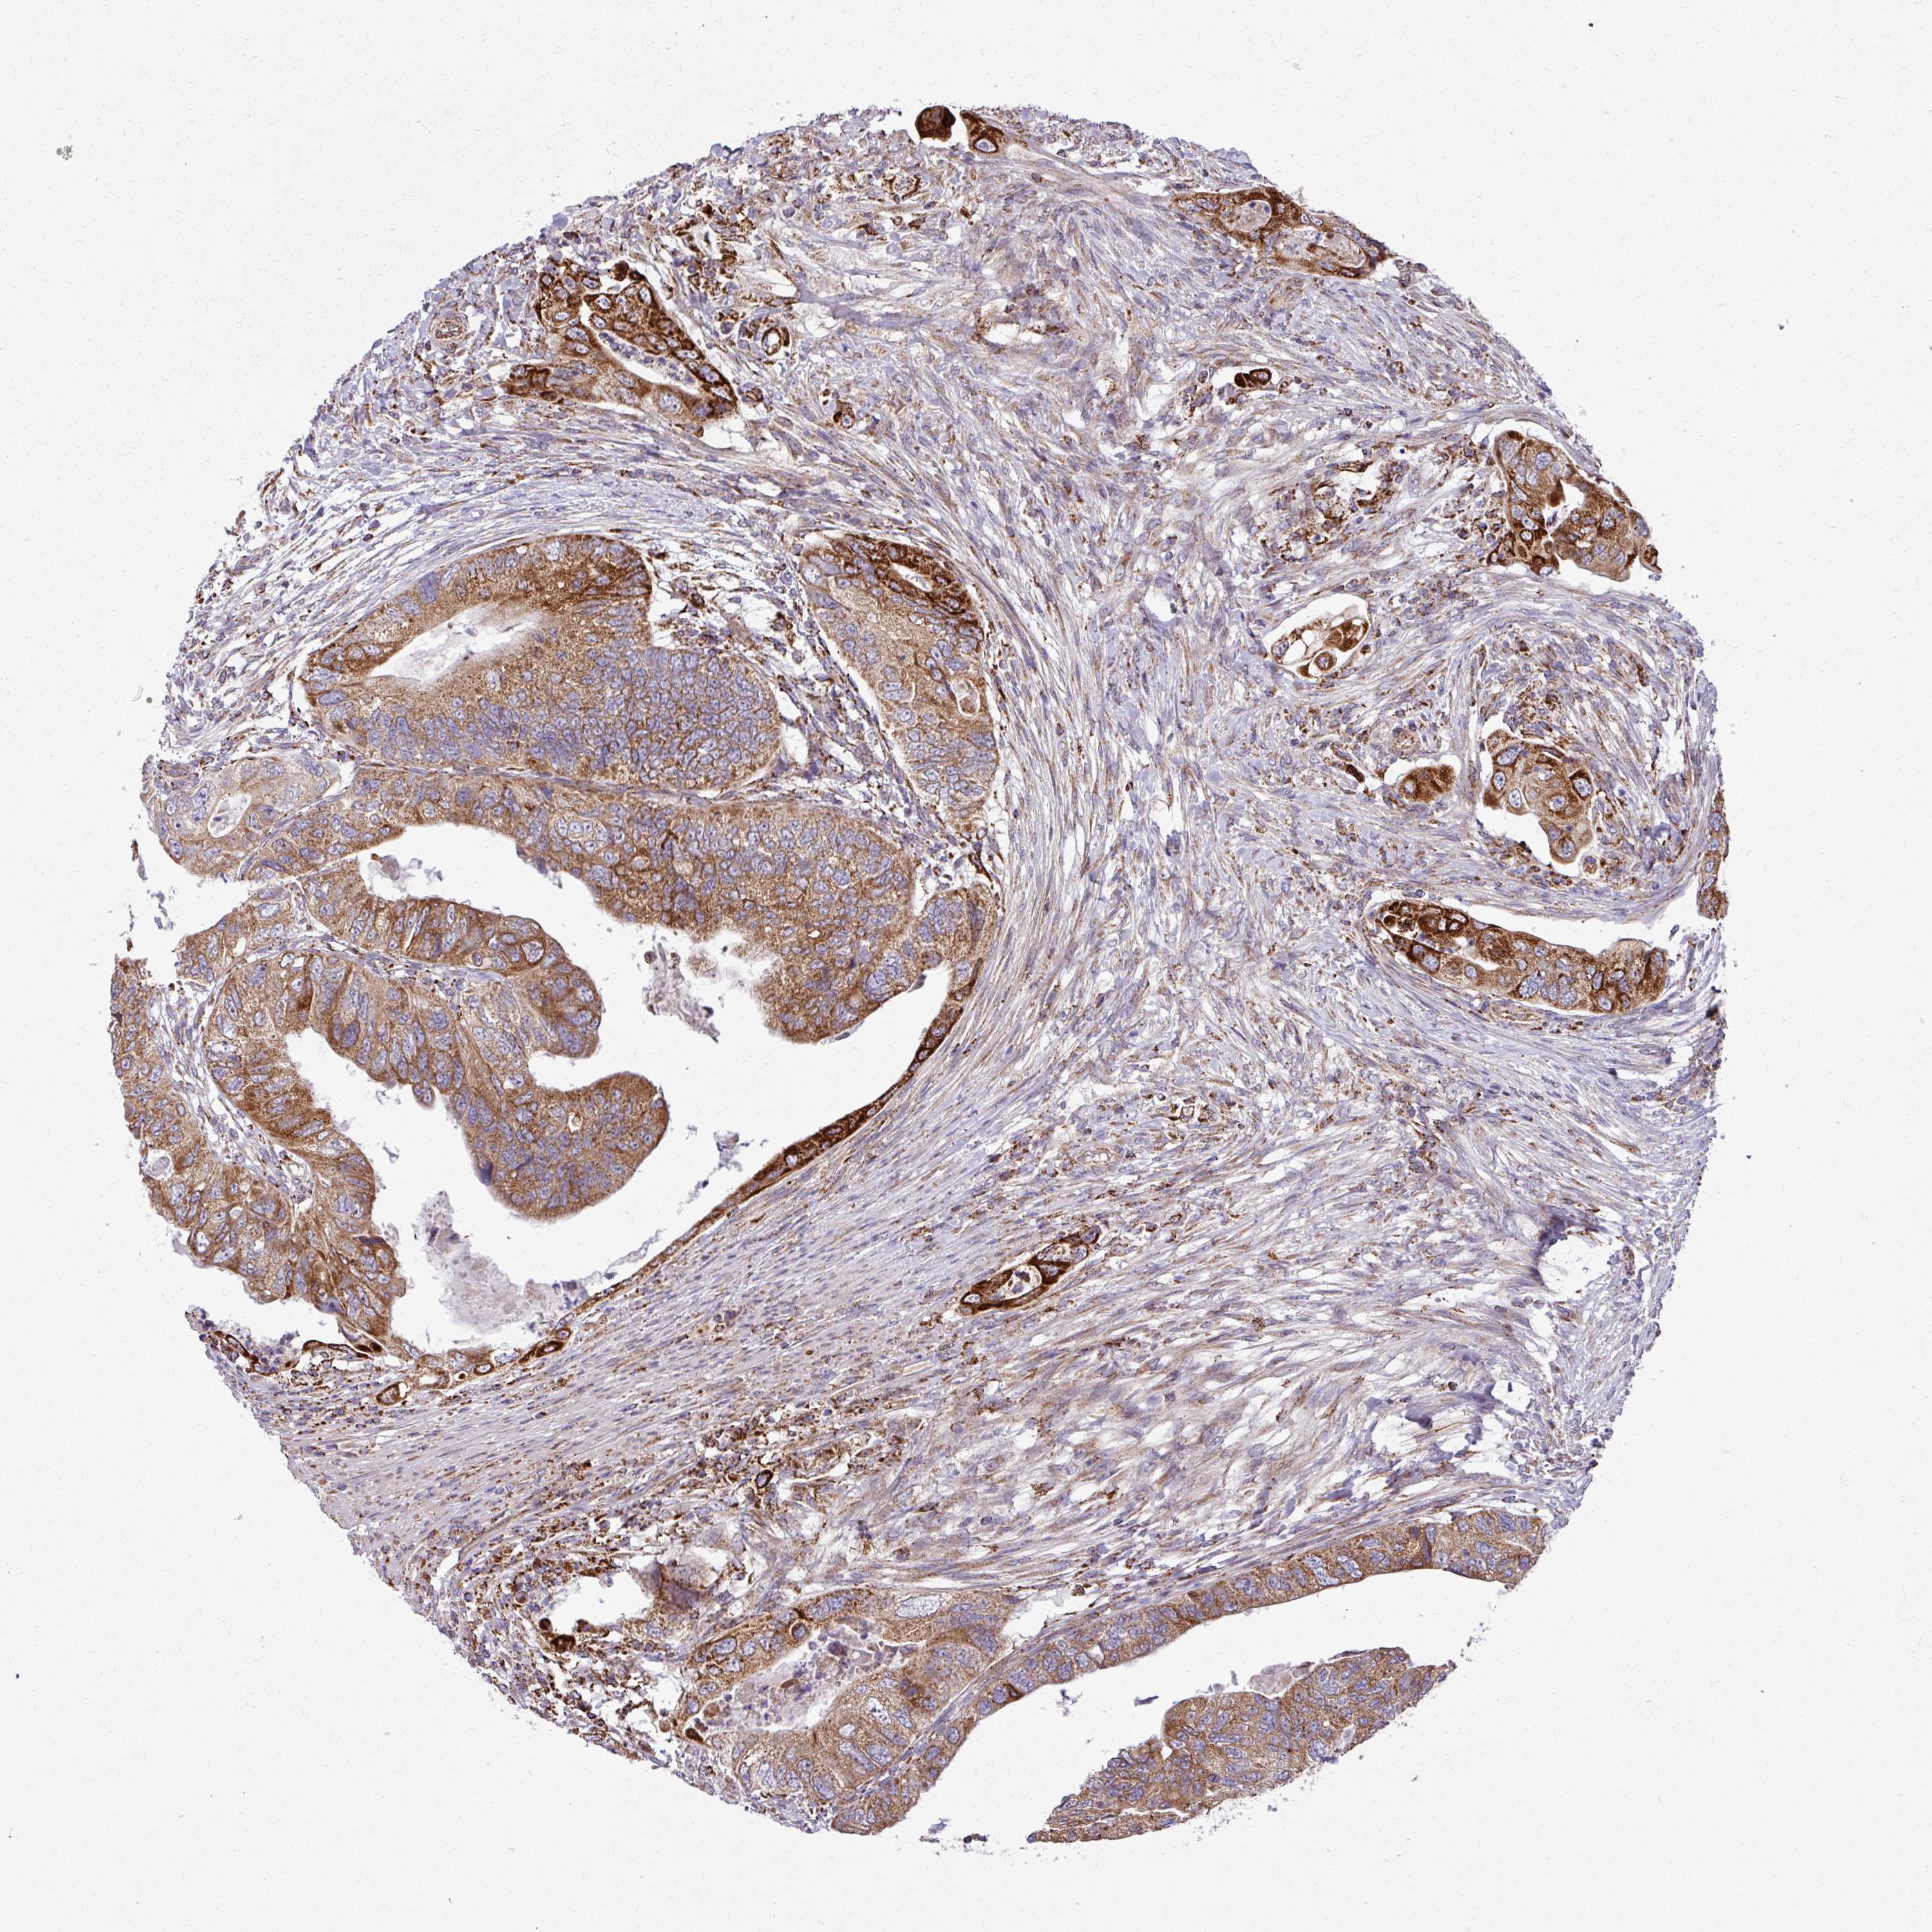

CANCER COLORECTAL CANCER Show tissue menu

Colorectal cancer

Human cancer

Colon adenocarcinoma